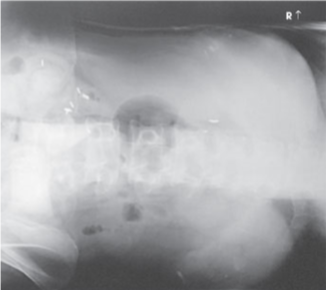

What projection, position, and anatomy is this?

AP KUB